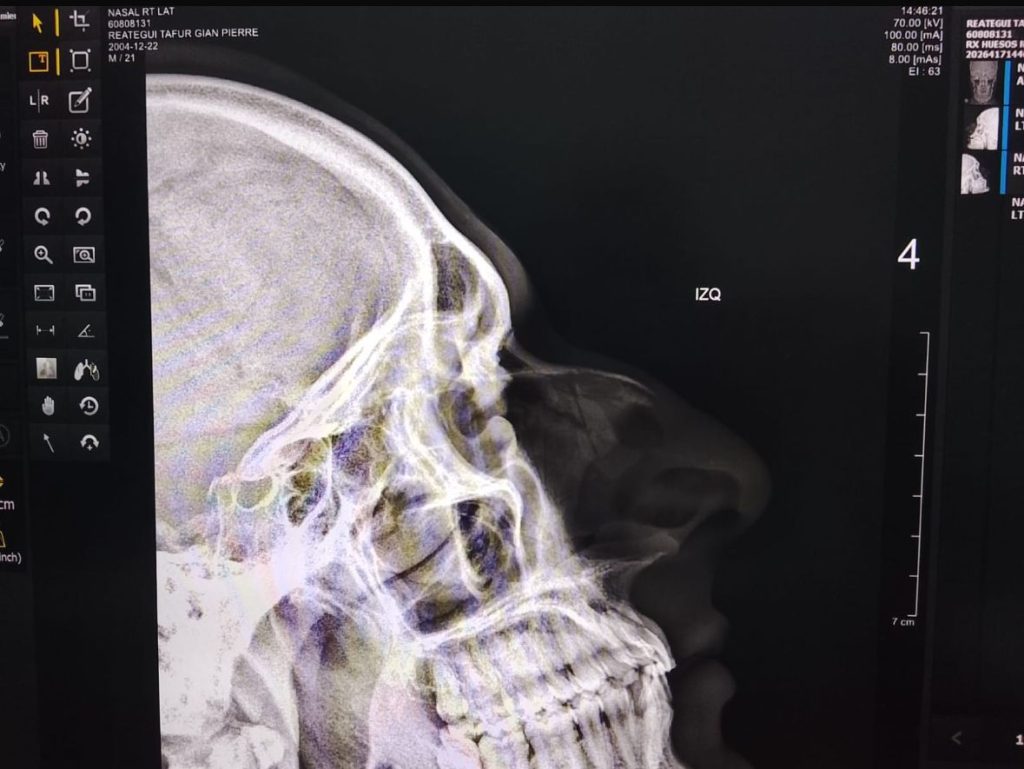

De acuerdo con la información disponible, el intervenido fue trasladado tras su detención; sin embargo, durante su permanencia en dicha dependencia habría protagonizado un violento ataque contra el suboficial de tercera Jean Pierre Reátegui Tafur, a quien presuntamente le propinó un rodillazo que le ocasionó la fractura del tabique.

El suboficial Reátegui Tafur permanece en proceso de recuperación debido a la lesión sufrida, la cual requeriría tratamiento especializado e inmovilización, lo que también afecta su capacidad de servicio en la institución policial.